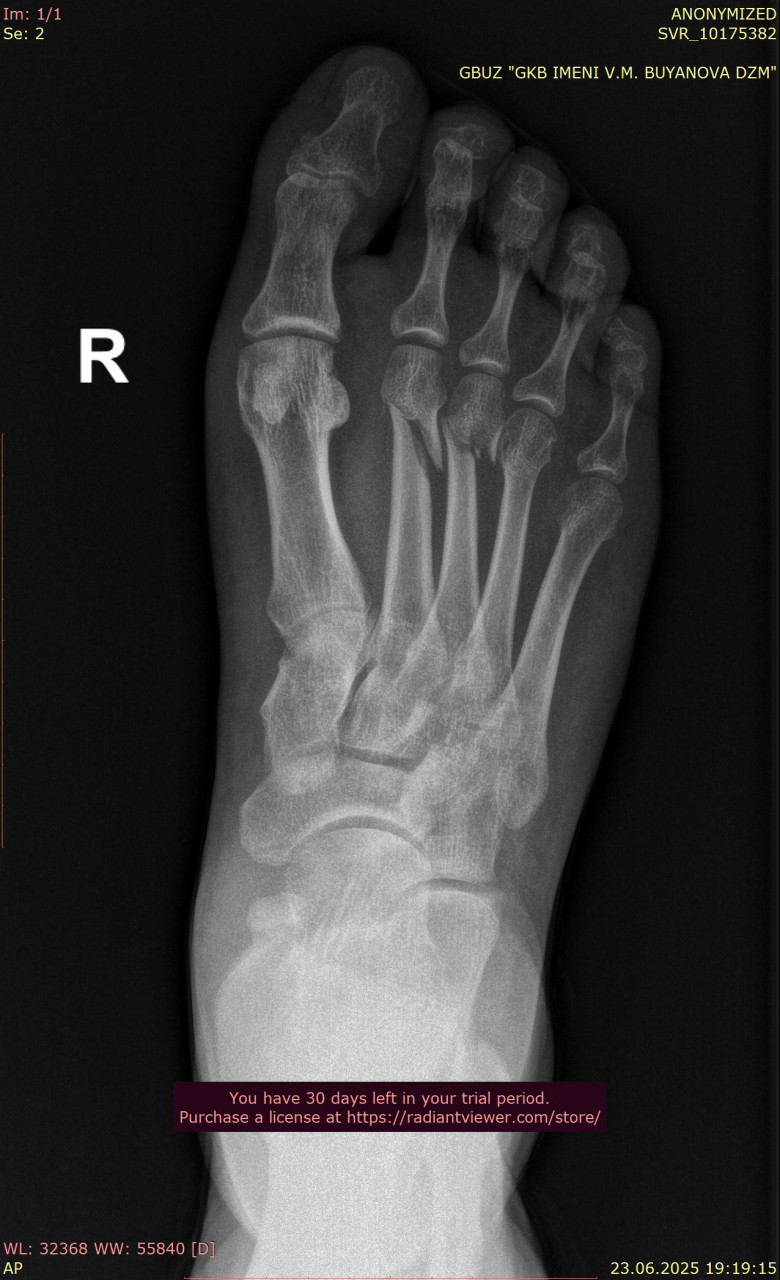

Прикрепляю снимки стопы от даты перелома 23.06.2025 (одна проекция из за лимита файлов на сайте} , и спустя 3 месяца от 24.09.2025. Как Вы считаете, переломы зажили окончательно, проблем быть не должно? В дополнение про выбор стелек: в ортопедическом салоне можно просто сказать, что у меня остеоартроз голеностопного сустава и попросить недорогие стельки по размеру?

Здравствуйте. На новых снимках переломы срослись, кость выглядит восстановленной, грубых осложнений не видно. Проблем при обычной нагрузке быть не должно. В салоне действительно можно сказать про остеоартроз голеностопа и подобрать недорогие готовые стельки по размеру и этого на начальном этапе будет достаточно.